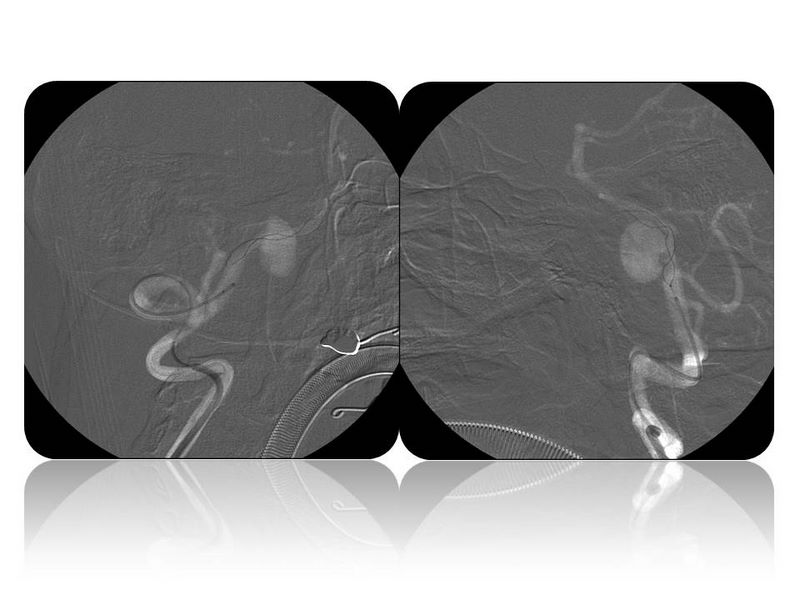

Aneurismas grandes